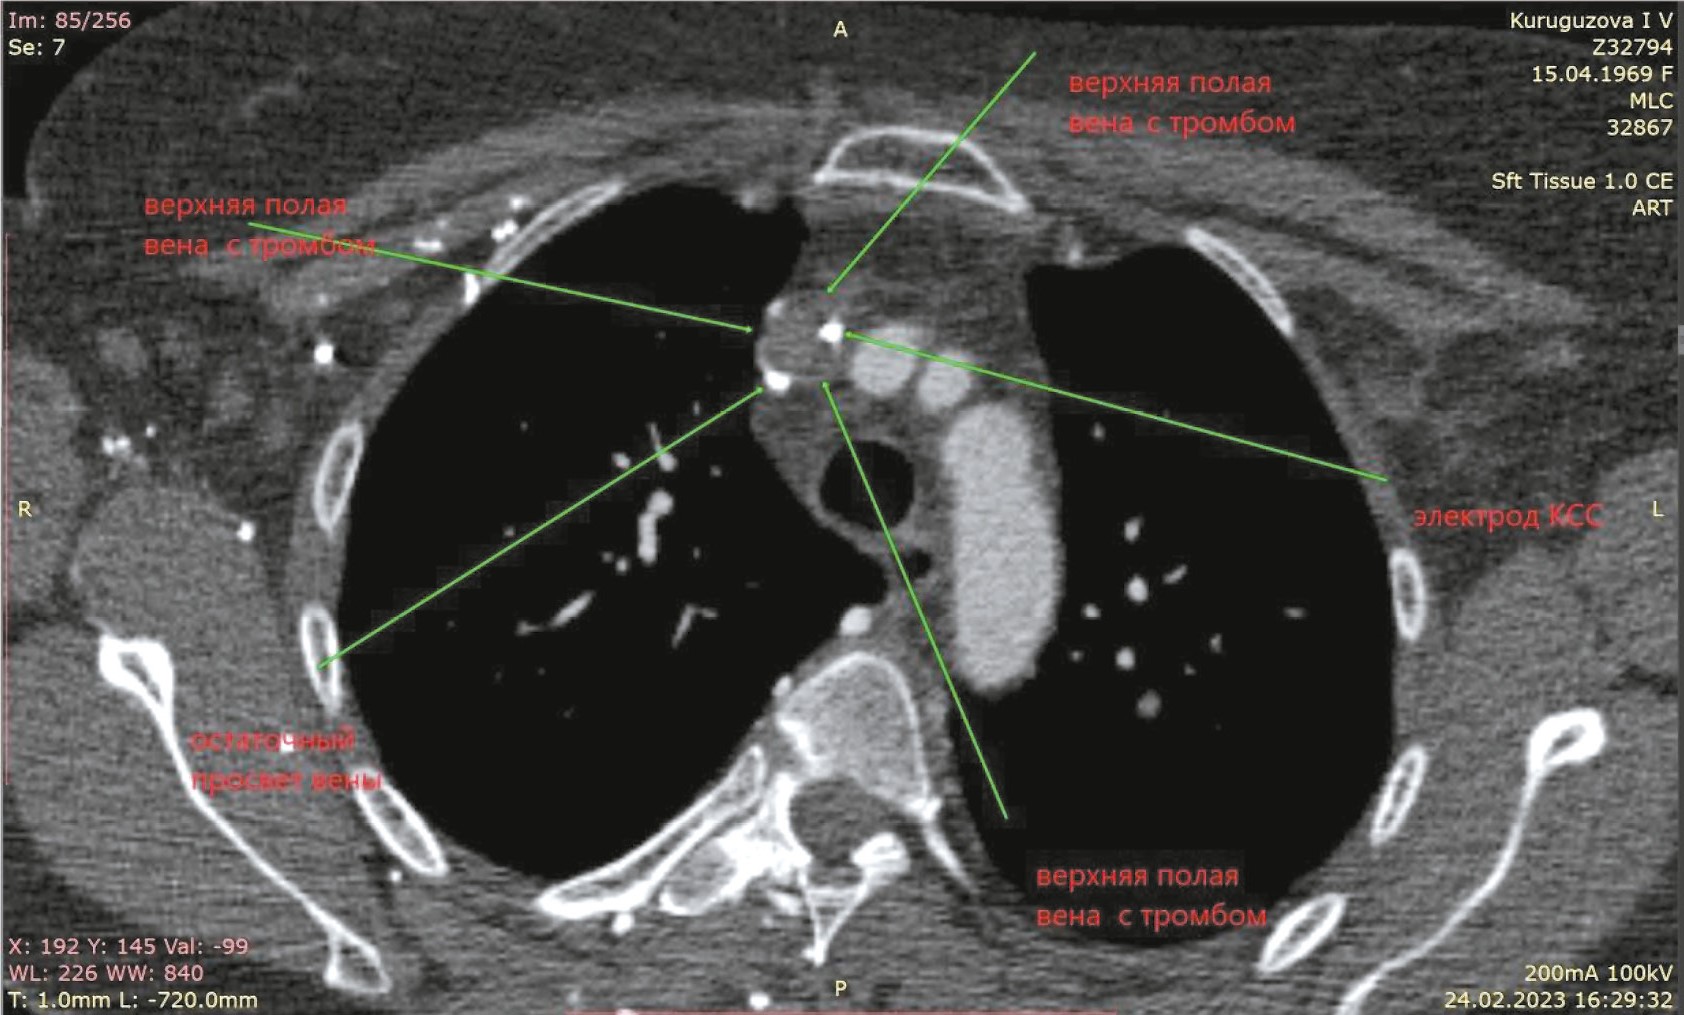

Рис. 1. Компьютерная томограмма пациентки К. Верхняя полая вена, просвет которой почти полностью заполнен тромботическими массами.

Fig. 1. Computed tomography of patient K. Upper vena cava, the lumen of which is almost completely filled with thrombotic masses.

Обращает на себя внимание выраженная задержка контраста в венах правой верхней конечности, куда вводилось контрастное вещество. Имеется богатая ветвь венозных анастомозов в мягких тканях грудной клетки, паравертебрально. ВПВ уменьшена в диаметре, её просвет практически полностью заполнен тромботическими массами от уровня впадения левой подключичной вены до места впадения непарной вены, сохранён просвет в виде узкой (1×4 мм) полулунной щели вдоль электрода. Непарная вена расширена, имеет диаметр до 10 мм и практически полностью обеспечивает верхний приток крови к правому предсердию. Основное возвращение крови к сердцу происходит через нижнюю полую вену, заполнение контрастом которой заметно отсрочено. Заключение: картина тромбоза/субтотальной облитерации ВПВ с организацией коллатерального венозного кровотока. Состояние после установки электрокардиостимулятора (ЭКС). Дилатация левых отделов сердца.